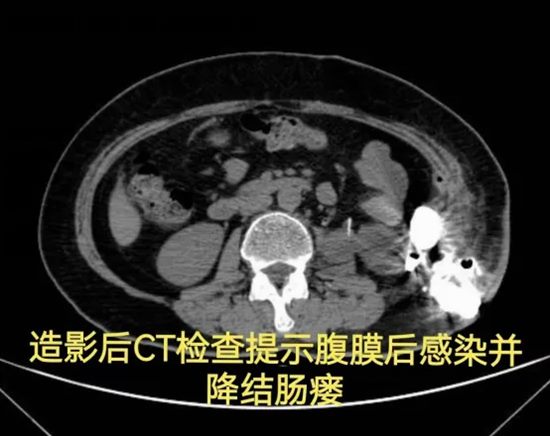

病情简述:56岁女性,两次腹膜后手术后出现降结肠瘘。

诊疗破局:按传统疗法,需先做结肠造口(挂粪袋),等半年后再做二次手术还纳。为减轻患者痛苦,团队制定“清创、控感、一期修复”三步法,实施腹腔镜下瘘切除+一期结肠端端吻合术。术后一周患者正常进食,免去了半年造口之苦。

技术体现:精准的术前评估与微创技术,让创伤最小化与疗效最大化不再是单选题。